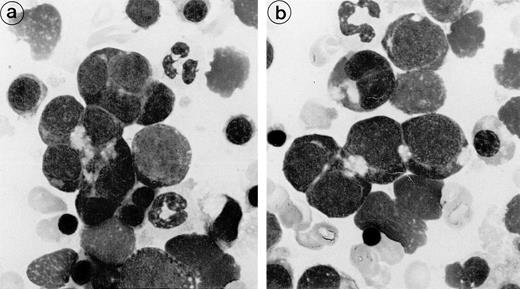

Bone marrow aspirates from the 3 patients showed marked hypercellularity and erythroid hyperplasia (>70% for case nos. 1 and 2). Bone marrow smear from patient 3 showed diffuse lymphocytic infiltration (86%) and numerous erythroid islands (Fig1). The main abnormalities observed in the bone marrow smears of the 3 patients were the presence of numerous erythroid islands, with aggregated erythroblasts and frequent binuclear forms. Most often, adjacent cells shared the appearance of the same maturation stage, but some cells of apparently different maturity were also in close contact. A nonbasophilic clear area was observed at sites of close proximity between adjacent erythroblasts. This feature allowed a distinction to be made between this type of erythroid island and that of sideroblastic anemia. No macrophages were found in contact with these erythroblast clusters.

Bone marrow smear (patient 2): The erythroblasts are numerous and several of them are closely apposed to each other. At the intercellular junction, a clear nonbasophilic zone is evident.

Bone marrow smear (patient 2): The erythroblasts are numerous and several of them are closely apposed to each other. At the intercellular junction, a clear nonbasophilic zone is evident.

The erythroblastic synartesis could be reproduced in vitro: indeed, erythroblast cultures established with bone marrow progenitors from cases 2 and 3 displayed similar morphological abnormalities to those observed in vivo (Fig4a, see page 3686). Crossed culture experiments using the patient erythroblasts grown in the presence of their own serum or of a control serum, or using erythroblasts of a control subject grown in the presence of the patient sera (see Table1) were performed and gave the following results: the erythroblast abnormalities reproduced in culture in the presence of autologous serum were absent when the culture was performed with a control AB serum (Fig 4b). Electron microscopy confirmed these findings, showing that the same intercellular junctions were observed when the patient erythroblastic progenitors were cultured with autologous serum, but that they were absent when the culture was performed in the presence of a control serum. These abnormalities were not reproduced in vitro when the erythroblasts were grown in the patient sera that had been IgG depleted. This allowed us to conclude that the synartesis was caused by an IgG component. Further confirmation was given by the observation that cultured normal erythroblasts displayed authentic synartesis when grown in the presence of patient to serum. Finally, the IgG fractions from the patients were added to normal serum at a concentration of 2 g/L and were able to induce typical synartesis on control erythroblasts grown in this preparation (Fig 5).

Light microscopical aspect of the erythroblasts cultured from patient 2 bone marrow. (a) In the presence of autologous serum: The erythroblasts are closely apposed to each other with occasional nonbasophilic areas present at their junction, mimicking the morphology of the bone marrow smears. (b) In the presence of a control serum: The grown erythroblasts are scattered and individually disposed on this cytospun preparation and do not display the characteristic abnormalities of the disease.

Light microscopical aspect of the erythroblasts cultured from patient 2 bone marrow. (a) In the presence of autologous serum: The erythroblasts are closely apposed to each other with occasional nonbasophilic areas present at their junction, mimicking the morphology of the bone marrow smears. (b) In the presence of a control serum: The grown erythroblasts are scattered and individually disposed on this cytospun preparation and do not display the characteristic abnormalities of the disease.